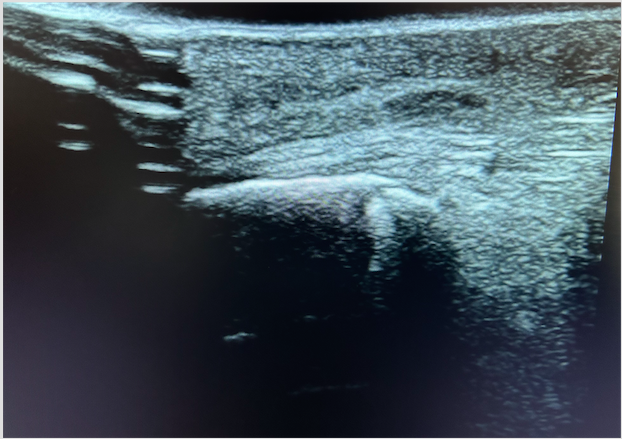

Eco musculoesquelético: Se visualiza línea hiperecogénica que atraviesa perpendicular a la cortical compatible con fractura de rótula. Tendón rotuliano ligeramente anecoico en inserción, sin datos de rotura.

Se solicita Rx para completar estudio.